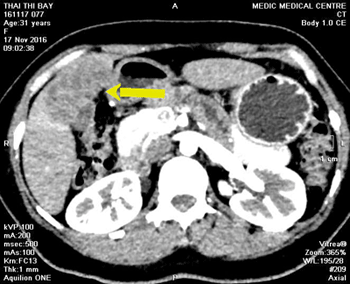

-Chụp đa lát cắt (MSCT_Multislice computed tomography) tổng quát bụng cho thấy gan không to, chủ mô gan đồng nhất. Hạ phân thùy VI gan (P) có thương tổn giảm đậm độ, kích thước 4 x 6cm, đẩy lồi bao gan ra ngoài. Thương tổn dày thành đại tràng ngang gần góc gan, dày khoảng 20mm, bắt thuốc cản quang mạnh và xóa mờ mô mỡ xung quanh. Có vài hạch nhỏ kế cận kích thước 5- 10mm (Hình 2) à Chẩn đoán sơ bộ: Theo dõi ung thư đại tràng ngang xâm lấn xung quanh, di căn hạch và di căn gan. Chẩn đoán phân biệt: Tổn thương gan và đại tràng do ký sinh trùng.

Hình 2. Tổn thương giảm đậm độ gan (P) và dày thành đại tràng ngang